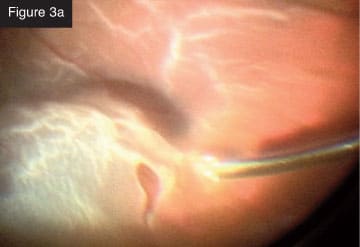

Membrane removal with vitrector. CASE 3: Total rhegmatogenous retinal detachment. I frequently combine scleral buckling with small-gauge vitrectomy. In a recent case of total rhegmatogenous retinal detachment (Figures 3a and 3b), I first did the scleral buckle and then removed the vitreous from the periphery with minimal traction on the retina. The creation of iatrogenic breaks is markedly reduced with this technology. I injected perfluorocarbon liquid and aspirated subretinal fluid. I like to aspirate often with the vitrectomy probe through the break. Next, I applied laser photocoagulation to the break. With the flexible tip laser probe, I find I can treat that entire area in an elegant, quick way, even in phakic

Rhegmatogenous retinal detachment.

Bidirectional laser to breaks. CASE 4: Tractional detachment in silicone-filled eye. Silicone oil removal and injection can be done beautifully through small gauge with the CONSTELLATION® System. In this case, I entered through the limbus to remove droplets of emulsified silicone oil from the anterior chamber (Figure 4a). Then, I used forceps to lift the membrane that was causing the tractional detachment (Figure 4b). After lifting off the membrane, I was able to remove everything with the cutter (Figure 4c). I still utilize forceps in some cases, but I use them less often with this technology.